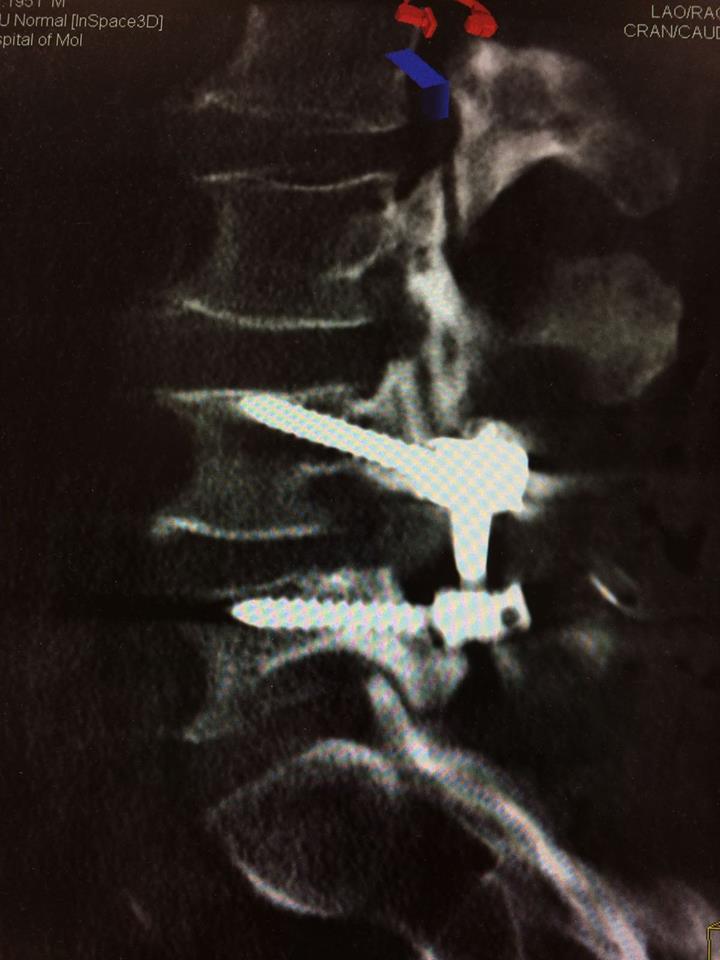

Echipa de specialiști în neurochirurgie spinală a Spitalului Clinic Republican a obținut o nouă realizare. S-a reușit o fuziune intervertebrală cu șuruburi transpediculare și cușcă intervertebrală printr-o incizie mai mică a pielii, de doar 4 cm, recordul anterior fiind de 5 cm. Succesul intervenției se datorează folosirii tehnologiilor moderne (CT intraoperatorie, Neuronavigația spinală, Neuromonitoring intraoperator) și planificării preoperatorii detaliate.

Pentru tratarea unui pacient de 63 ani cu diagnosticul de Spondilolistezis instabil L4-5, însoțit de stenoză de canal lombar, a fost folosit un abord chirurgical nou - Fuziunea Intervertebrală Mediană.